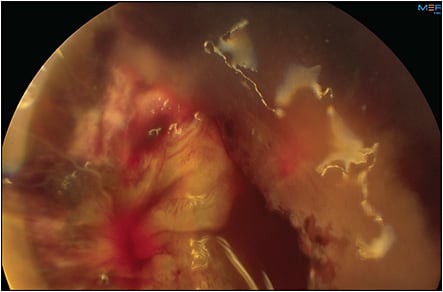

Because a patient on antithrombotics is at high risk from both ocular and systemic perspectives (Figures 1 and 2), it is important for a retina surgeon to have some working knowledge of the indications, management strategies, and pharmacology of commonly used antithrombotic agents. This review aims to provide retina surgeons knowledge and insight enabling them to effectively communicate these complex issues with patients and their medical providers to strive for the best possible outcomes for each patient.

Certain retinal surgeries, such as diabetic vitrectomy with extensive fibrovascular membranes, sutured IOL, scleral buckle with external drainage of subretinal fluid, chorioretinal biopsy, submacular surgery, surgery for hemorrhagic complications of peripheral exudative hemorrhagic chorioretinopathy, and proliferative vitreoretinopathy surgery involving large retinectomies may be at particularly high risk for perioperative bleeding (Figures 1 and 2). Other ocular factors that increase the risk of perioperative bleeding including suprachoroidal hemorrhage include myopia, glaucoma, inflammation, and hypotony.34,35